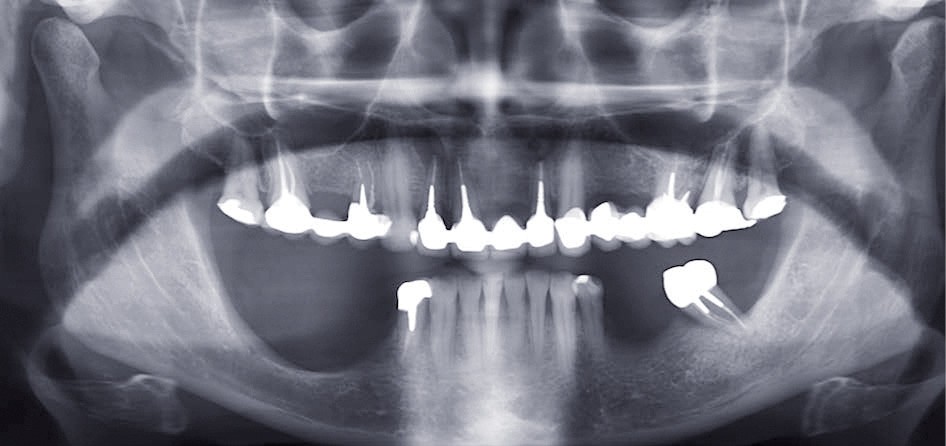

Examen radiographique